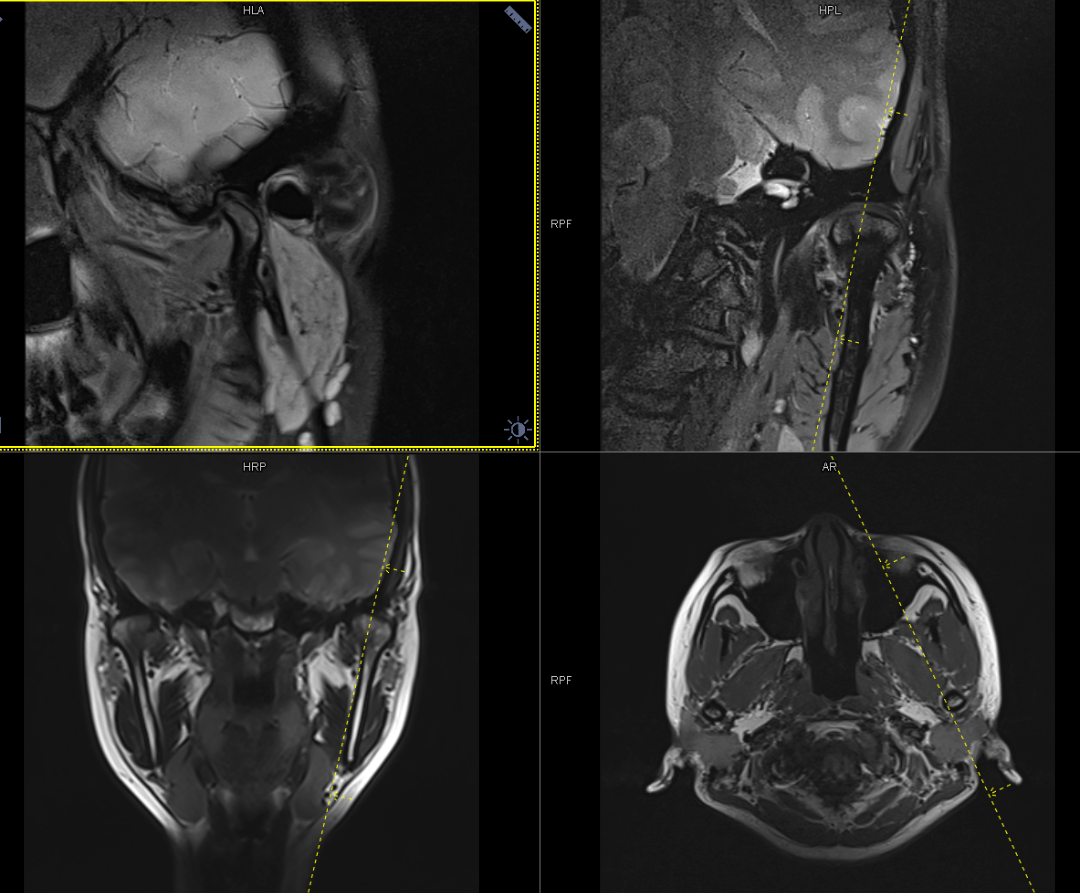

颞下颌关节ct扫描重建效果_磁共振

头颅正侧位,三维ct,双侧颞下颌关节的影像资料

本张照片显示tmj界面,对称性观察双侧颞下颌关节

【高尚病例】颞下颌关节紊乱的磁共振检查_扫描_患者_软组织